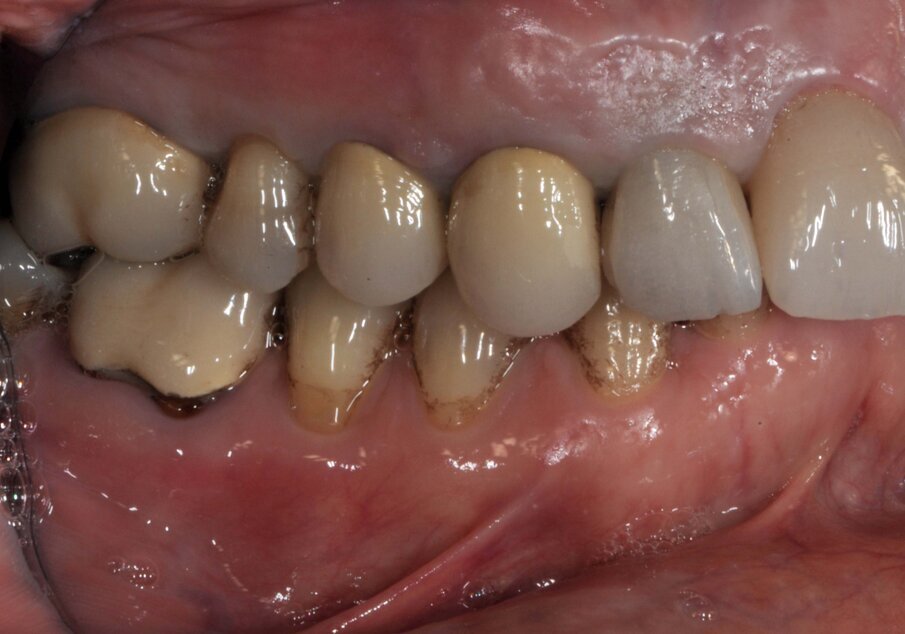

Il dente all’osservazione clinica e radiografica appare devitalizzato e ricostruito per mezzo di una perno moncone fuso e una corona in metallo ceramica collegata ad una corona sul dente 1.4 (Figg. 1, 2). All’esame parodontale si rileva un sondaggio puntiforme in zona palatale che indica la presenza di una frattura radicolare (Fig. 3). La paziente riporta una precedente apicectomia a carico del dente 1.2, come si evince dall’esame come-beam che ne evidenzia gli esiti a carico dell’osso apicale all’elemento 13 (Fig. 4).

Le corone sui denti 1.3 e 1.4 furono rimosse, il dente 1.3 fu estratto e l’alveolo fu riempito con una membrana di PRGF ottenuta tramite centrifugazione del sangue della paziente con il sistema Endoret e un provvisorio fu consegnato sui denti 1.3 e 1.4 (Fig. 5, 6). Dopo otto settimane fu eseguita una nuova cone-beam e la chirurgia fu pianificata (Fig. 7). Si eseguì un lembo a tutto spessore, fu eseguita l’osteotomia e fu inserito un impianto BTI Core 3.5 × 8.5. Un pilastro Unit fu avvitato e un tappo di guarigione fu applicato. L’osso ottenuto dalla fresatura mescolato con una membrana di PRGF fu applicato sul lato palatale per compensare una piccola deiscenza, una seconda membrana fu applicata sopra l’osso circostante e un innesto di tessuto connettivo prelevato dalla tuberosità fu suturato vestibolarmente per ricreare la bozza canina. Punti di sutura staccati furono eseguiti con un filo in PTFE (Figg. 8-11). Dopo quattro mesi il provvisorio fu rimosso e i tessuti apparivano sani e con un buon spessore di tessuto connettivo vestibolare per garantire la stabilità nel tempo del risultato. Fu eseguita un’impronta con la tecnica del cucchiaio aperto e dopo due settimane furono consegnate una corona in zirconio cementata sul dente 14 ed una avvitata sul denta 1.3. Il profilo di emergenza della corona sull’impianto appariva ideale. Purtroppo, a causa della mancanza del picco osseo sul versante distale del dente 1.2, non si ottenne una papilla di altezza adeguata. Ciononostante la paziente si disse soddisfatta del risultato e rifiutò ulteriori terapie per correggere il difetto residuo (Figg. 12-15).